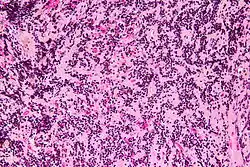

| Micrograph of a pineocytoma. HPS stain. | |